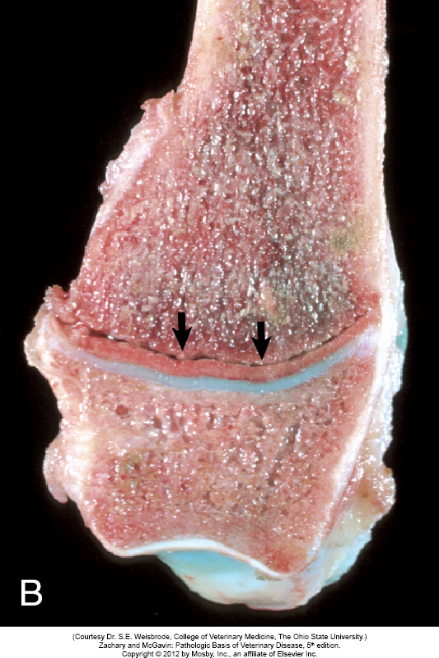

Artrose

Karakteristik: destruktion af ledbrusk (gulbrun farve), mat/ru overflade, svampet konsistens da vand er frit i brusken.

Årsager: traume, instabilitet, nedsat lubrikation, dyschondroplasi, inflammation (artritis), steroid behandling, alder.

Sekvela: Synovitis, villøs hypertrofi/hyperplasi, osteofyt-dannelse, subchondrale cyster, ledkapselfortykkelse, pannus-dannelse, ankylose, ledmus